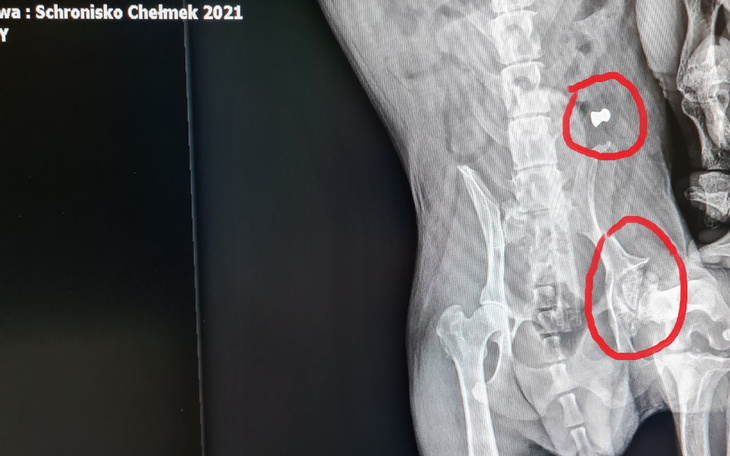

Nasza organizacja pomaga bezdomnym porzuconym zwierzętom, które wymagają opieki lekarsko weterynaryjnej. Ta zbiórka jest dla Teo. Teo to senior ( 8 lat), który przebywa w schronisku w Chełmku pod numerem 271/2021. We wrześniu piesek posmutniał, zaczął dużo polegiwać, nie chciał wychodzić na spacerki. Widać było, że boli go lewa tylna łapka. Nie pozwalał się dotknąć w tej okolicy. Teo trafił do lecznicy w celu diagnostyki. Wykonano zdjęcia rtg w znieczuleniu. Opis badania : pies postrzelony w okolicy lędźwiowej oraz martwica głowy kości udowej lewej z dużymi zmianami zwyrodnieniowymi.... Dość, że od urodzenia ten biedak zmagał się z chorobą genetyczną ( i walczył ze swoją ułomnością), to jeszcze jakiś człowiek go postrzelił.....